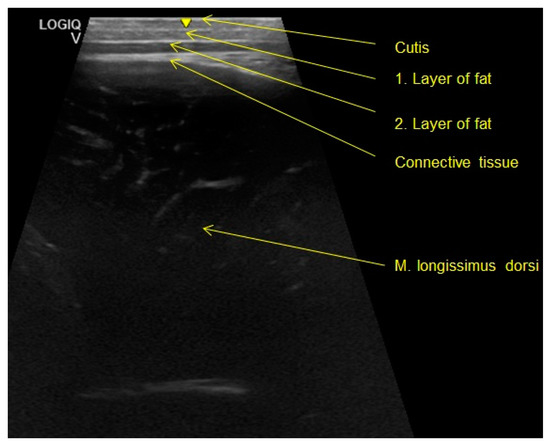

2.2.2. Ultrasound Examination